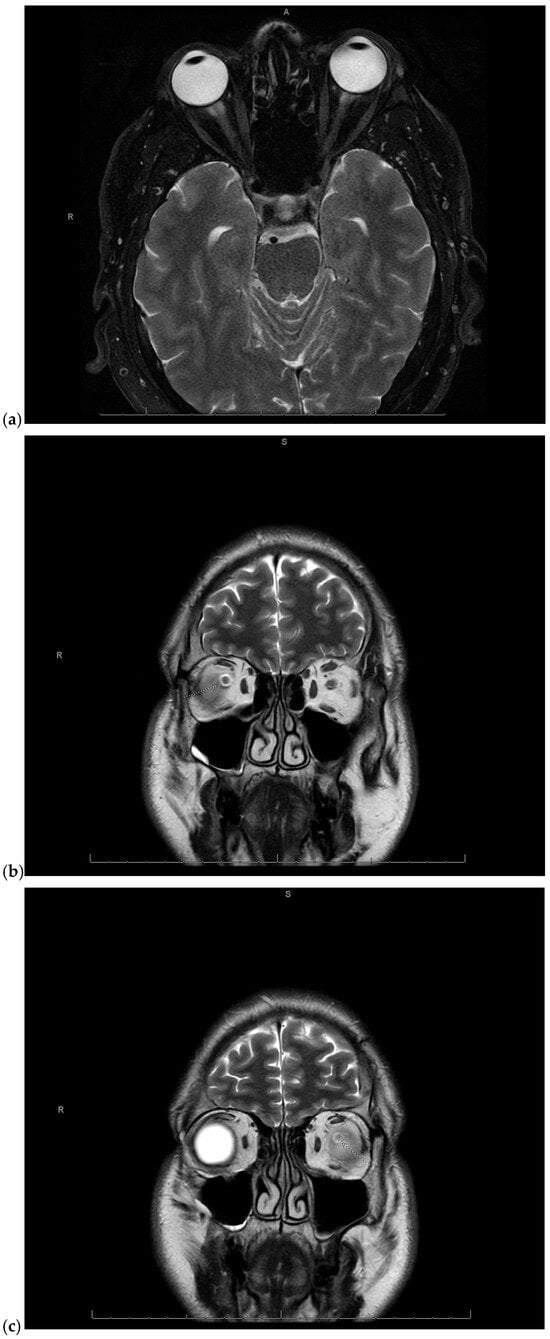

Given the concerning visual symptoms, the patient underwent an emergent magnetic resonance imaging (MRI) of the brain and orbits, which revealed T2 hyperintense signal abnormalities in the periphery of the optic nerves bilaterally, more pronounced on the right side, consistent with optic neuritis (Figure 1a–c).

Figure 1.

(a) Magnetic Resonance Imaging (MRI) of the brain and orbits fat-saturated T2-weighted axial image showing mild right greater than left T2 hyperintense signal in the periphery of the optic nerves in the anterior intraorbital region, consistent with optic neuritis. A: anterior, R: right; (b) MRI of the brain and orbits coronal T2-weighted image showing right sided optic neuritis. S: superior, R: right; (c) MRI of the brain and orbits coronal T2-weighted image showing left sided optic neuritis. S: superior, R: right.